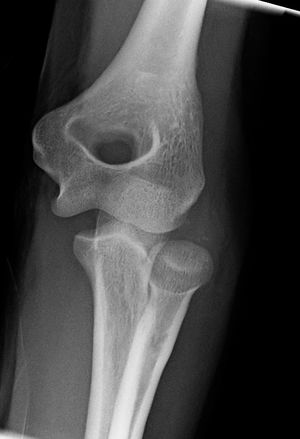

المرفق إنگليزية: Elbow هي عظمة مفصلية تربط عظمة العضد مع عظمتي الزند و الكعبرة. وتكون أماكن الالتقاء الثلاثة، ثلاثة مفاصل أصغر وتسمح هذه المفاصل الصغيرة بحركات معينة، حيث يسمح مفصلا العضد ـ الزند والعضد ـ الكعبرة للشخص بثني الساعد إلى أعلى وأسفل، بينما يسمح مفصلا الكعبرة ـ الزند والعضد ـ الكعبرة بدوران الساعد وكذلك راحة اليد أعلى وأسفل.

يحيط بمفصل الكوع كبسولة من نسيج متين. وتقوم هذه الكبسولة مع عدد من الأنسجة القوية الحبلية الشكل التي تُعرف بالأربطة بالمحافظة على العظام في أماكنها. ويعمل السائل الزيلي بمثابة مزلق لتقليل الاحتكاك عند الكوع.

يتسبب الالتواء الزائد أو العنيف للساعد في إصابة أربطة الكوع، أو السائل الزليلي. تسمى هذه الإصابة كوع التنس لأنها كثيرًا ما تحدث في لعبة التنس. وقد تحدث زحزحة للكوع إذا ما سقط شخص ما على ذراعه الممتدة.